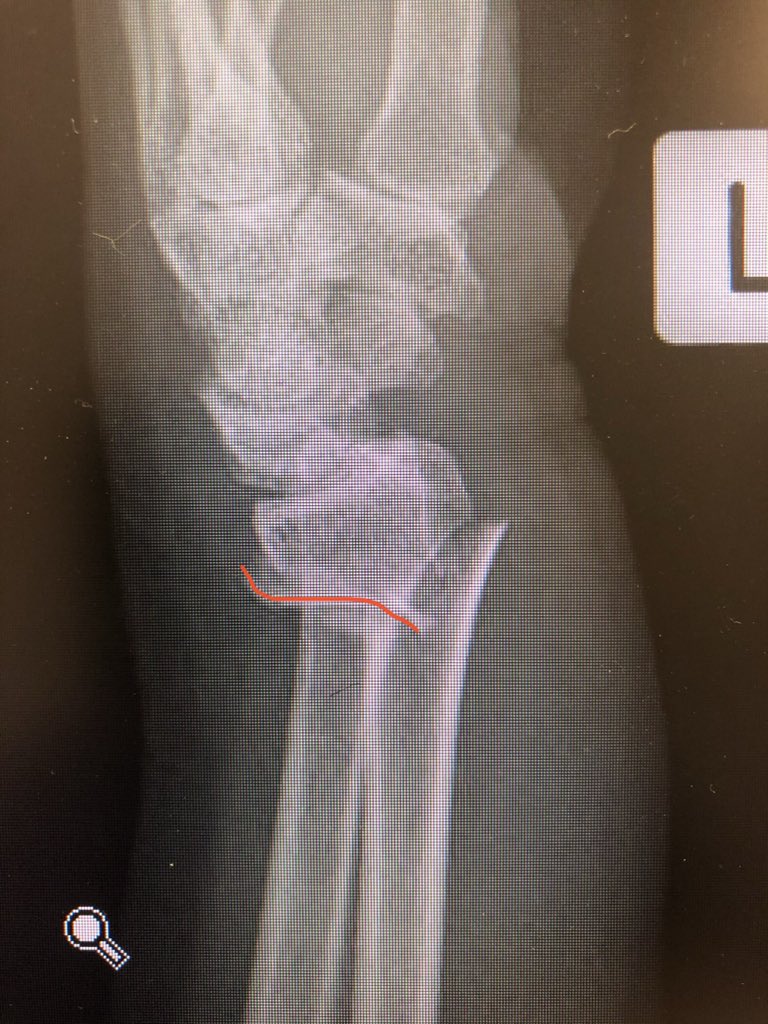

Simple everyday distal radius fracture. 60 yr old nurse. Medically well. #OrthoTwitter

I see conventionally this would be called an ‘extra-articular’ fracture.

Point 1:

The proximal fragment radius spike has a risk of translational mal-reduction and this can bother rotation of the forearm.

Reduce this by putting a ‘lamina spreader’ in the inter-osseus space Before locking the shaft screws and clear the DRUJ.

Point 2:

The dorsal metaphyseal comminution. The dorsal cortex fragment is ‘fallen in’ inside the osteoporotic metaphyseal void.

I addressed this after plating finished, made a 4.5 mm drill hole in the ‘window’ of the plate to push the fragment and fill in graft substitute.